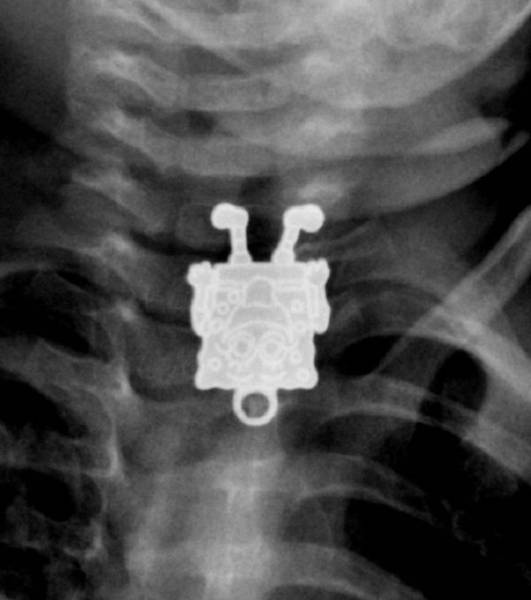

Lääkärit katsoivat nämä röntgenkuvat ja joutuivat hieraisemaan silmiään: 22 eksoottista kuvaa

Röntgenkuvat voivat paljastaa tärkeitä yksityiskohtia ihmisen terveydestä. Joskus ne havaitsevat kuitenkin myös asioita, joita ihmiskehon sisällä ei todellakaan kuuluisi olla.

Lääkärit saivat varmasti hieraista silmiään, kun he katselivat näitä röntgenkuvia. Toki joissakin tapauksissa tiedettiin jo, mitä etsiä, mutta osa tuli varmasti yllätyksenä.

Näiden kuvien jälkeen voin todeta, että olen nähnyt kaiken!